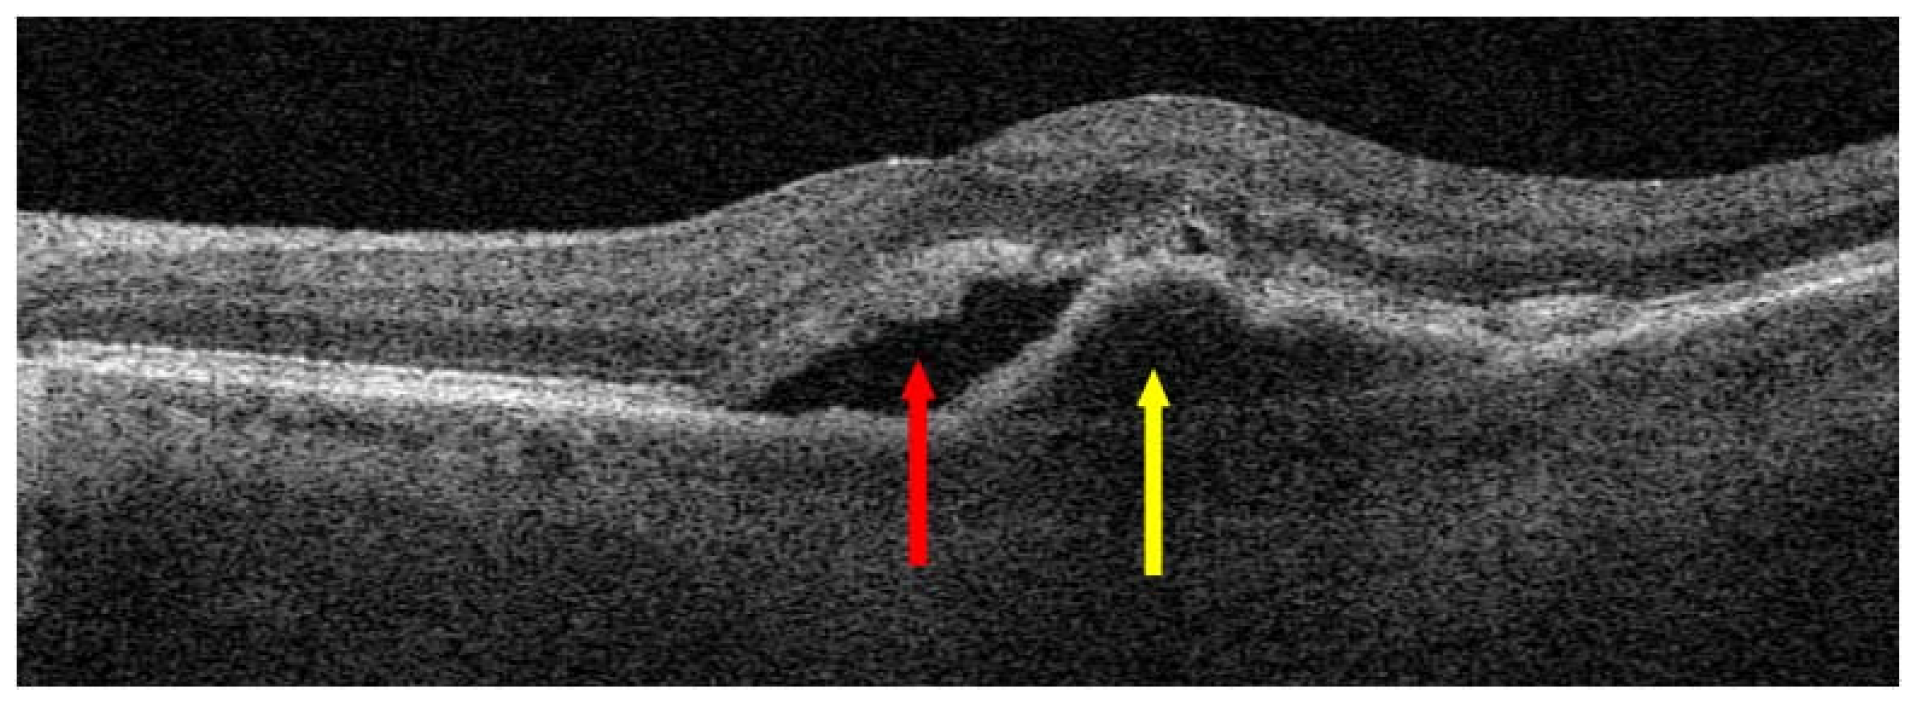

3. Treatment of Neovascular AMD

3.2. Anti-VEGF Drugs

3.2.1. General Information

3.2.2. Anti-VEGF Therapies